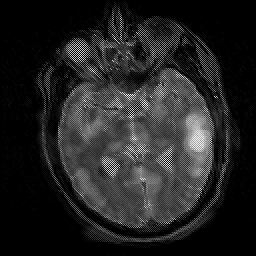

Subacute Stroke, overlay -- Slice #11

[Home][Help][Clinical] Slice 11